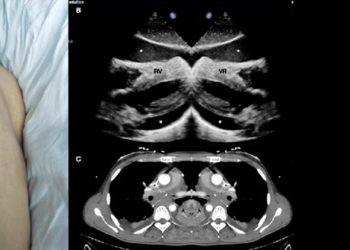

- X-rays: To detect facial or nasal fractures.

- CT scan: Recommended if there is concern about orbital fractures, brain injury, or internal bleeding.